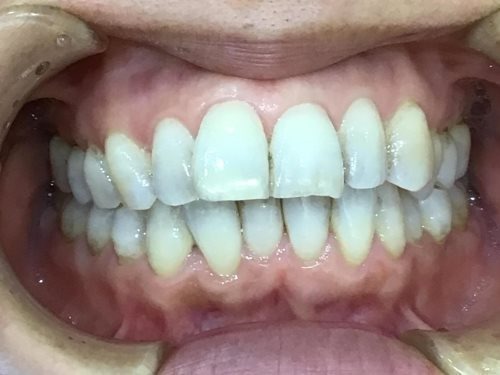

正面